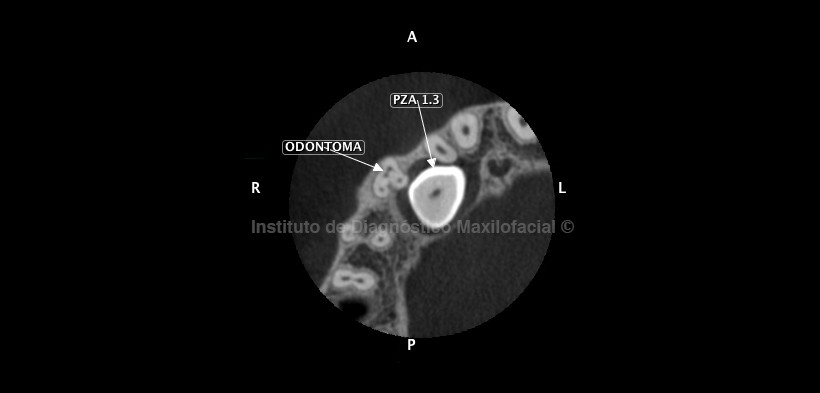

Al estudio de la tomografía volumétrica de haz cónico (cone beam), en la vista coronal se aprecia la relación de esta lesión con la pieza 1.3, lo que condiciona el posicionamiento en vías de erupción hacia palatino y el consecuente retraso en la reabsorción radicular de la pieza 5.3. (Fig. 2)